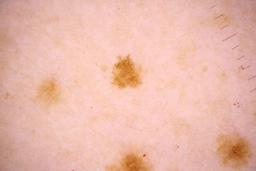

Evaluation set from the ML challenge: SIIM-ISIC Melanoma Classification.